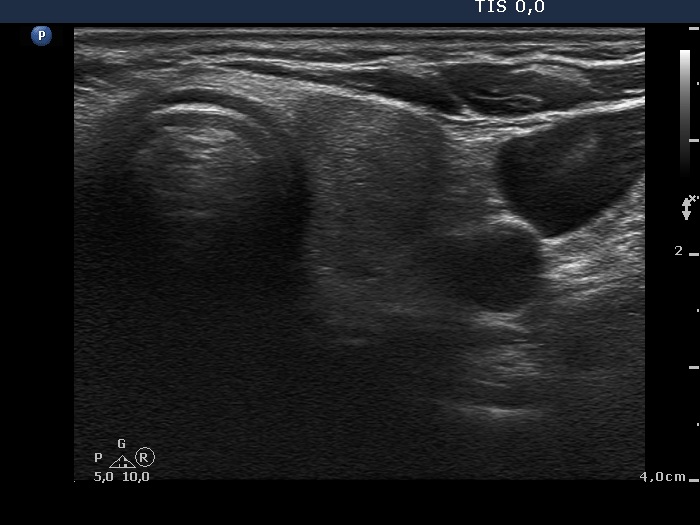

Ultrasonography: the thyroids were moderately hypoechogenic and contained several discrete, circumscribed lesions. There was a hyperechogenic nodule in the lower part of the right lobe while a cystic nodule in the upper part of the left lobe.

The thyroid is hypoechogenic and is surrounded with a relatively thin echonormal rim. This makes an appearance if both lobes were composed of a large hypoechogenic nodule. However, the echonormal rim corresponds to thickened connective tissue; a frequent phenomenon in an operated thyroid.

The upper part of the right lobe seems to be nodular, i.e. composed of two nodules at first sight. However, an insertion of the connective tissue and an acoustic shadow of a coarse calcification divides this part of the thyroid to two lesions. These do not fit nodules in a pathological sense.